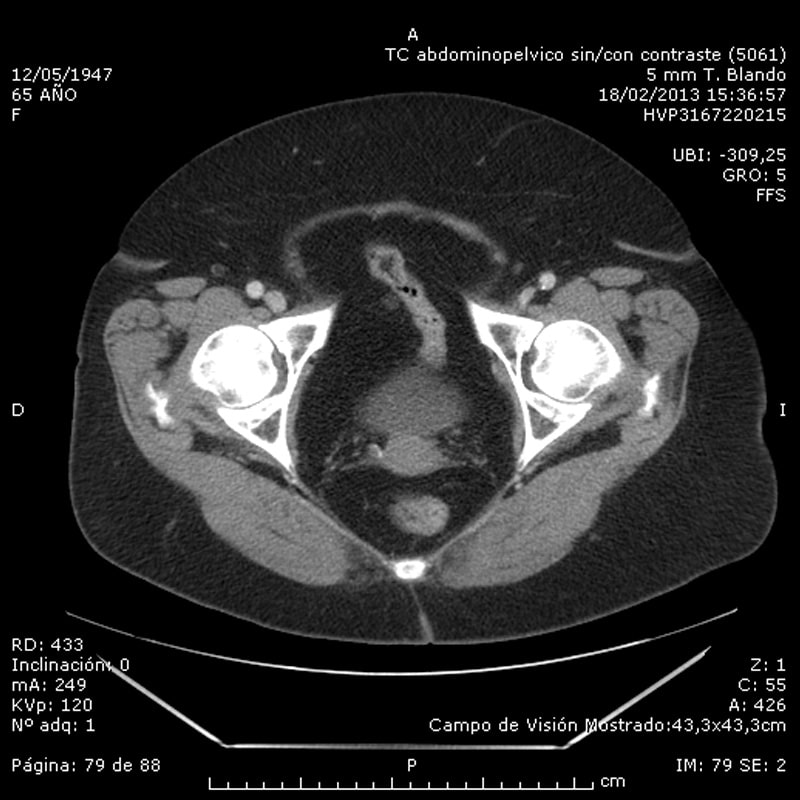

Analytisk sett forblir blodtellingen (leukocyttall og formel) og biokjemi (inkludert bilirubinemi og amylasemi) normalt. En evaluering er forespurt for kirurgi som ber om en beregnet tomografi av magen som viser vridningen av et lite epiploisk vedlegg ved siden av sigmoid-kolon. (Figur 1).

Beregnet tomografi abdominopelvic Poliklinisk behandling med flytende diett, amoksicillin-klavulansyre 500 mg hver 8. time muntlig i 8 dager og gjennomgang i ambulant kirurgi innen 15 dager er indikert.

Pasienten går for asymptomatisk revisjon. Den radiologiske kontrollen som ble utført (abdominal CT med kontrast) var normalt (figur 2).

Den diagnostiske teknikk er abdominal CT utbredt og som et verktøy for diagnose av akutt magesmerter nødstilfelle er den mest følsomme og spesifikke testen gir patognomonisk funn som i vårt tilfelle, TC bemerket omental tillegget som en avrundet bildeintensitet avhengig colonic serosa med rundtgående fremspring av denne, og ledsages av en fortykning av parietal peritoneum og / eller fett tykktarm vegg. Behandlingen bør være konservativ gjennom analgetika, orale antiinflammatoriske stoffer og hvile, med en tendens til å løse symptomene uten å kreve kirurgisk behandling eller antibiotika. Prognosen for denne enheten er utmerket, det kliniske bildet varer vanligvis ikke mer enn to uker, selv om de radiologiske funnene kan vare fra uker til flere måneder. Bør ta hensyn til mulige komplikasjoner som appendicular torsjon adhesjon til nabo innvollene kan forårsake abscesser eller intestinal obstruksjon, og i dette tilfelle bør kirurgisk behandling.